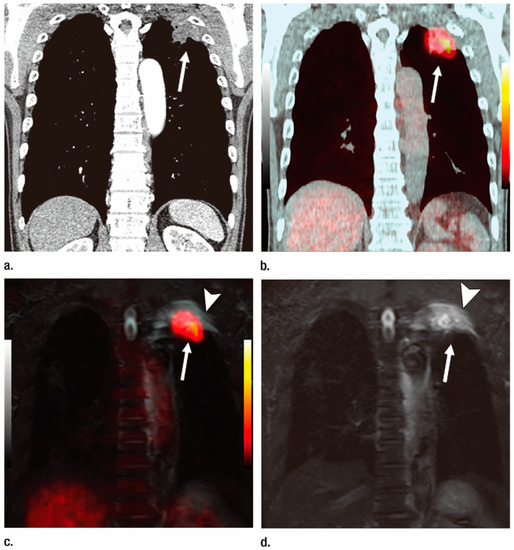

2.1. T-Factor Assessment

2.2. N-Factor Assessment